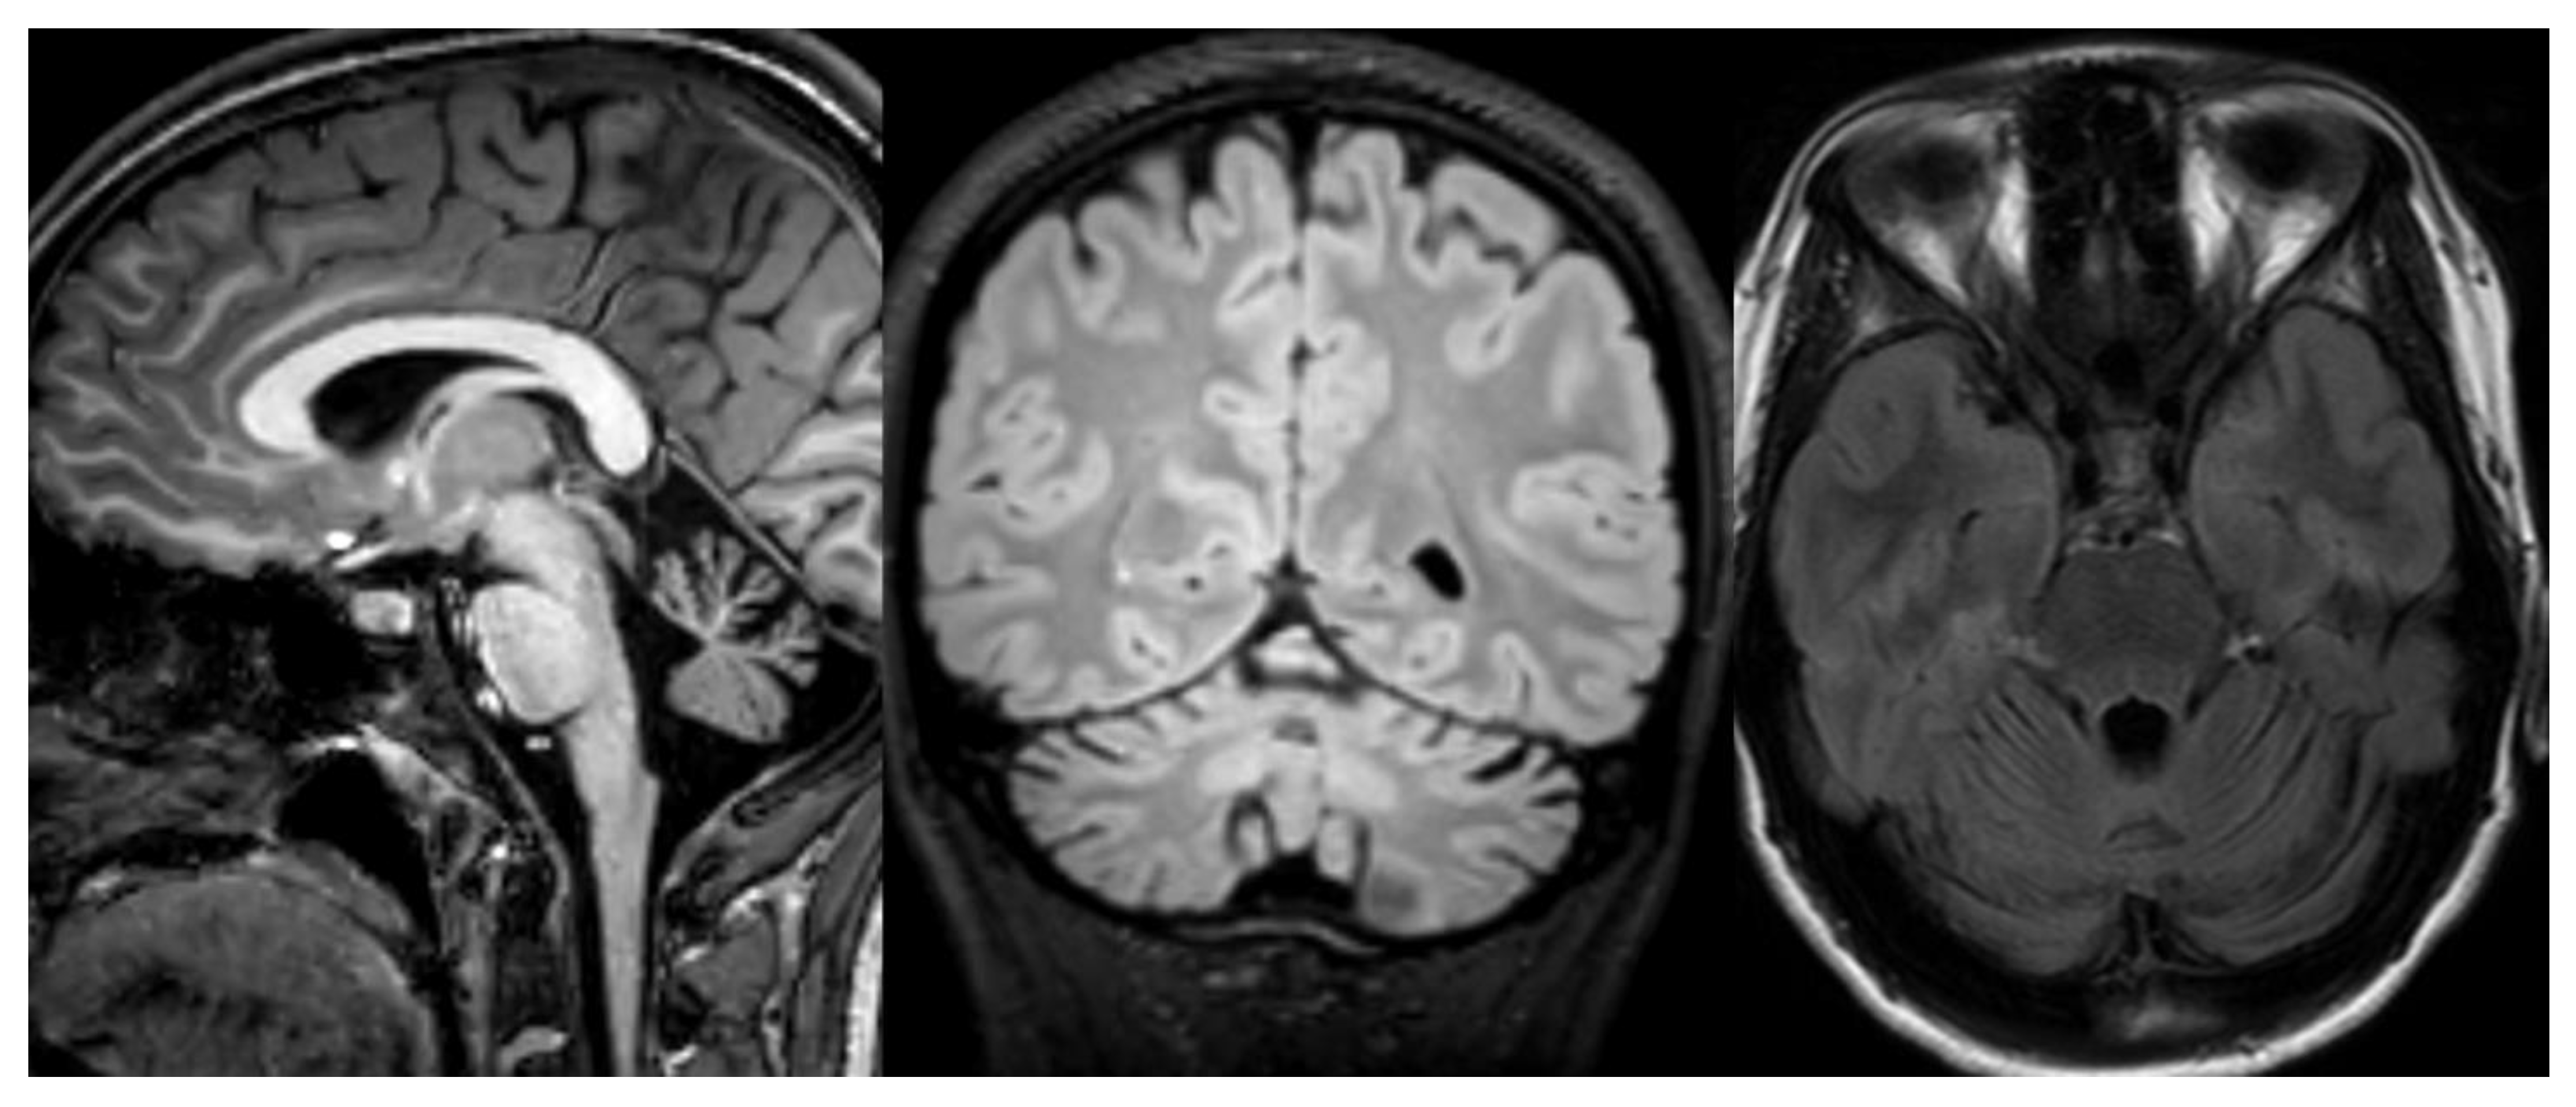

CACNA1G calcium channel is known to cause adult-onset spinocerebellar ataxia [42]; recent works report cerebellar ataxia associate with mutations in this gene [48,49]. MRI shows cerebellar atrophy [49] (Figure 9).

Figure 9.

CACNA1G mutation. Brain MRI scan of an 11-year-old girl. MR images demonstrate not specific diffuse cerebellar atrophy.

2.2. H-ABC (Hypomyelination with Atrophy of Basal Ganglia and Cerebellum)

H-ABC is an autosomal dominant hypomyelination leukodystrophy due to TUBB4A mutations [52]. The characteristic clinical features are progressive dystonia with early onset associated with cerebellar and pyramidal signs and cognitive deficiency. Neuroradiological findings combine diffuse cerebellar atrophy, hypomyelination, and typical basal ganglia abnormalities characterized by progressive neostriatal atrophy, with a normal size of the pallidum and thalamus, until almost complete disappearance of the putamina and caudate [53] (Figure 10).

Figure 10.

HABC. Brain MRI scan of a 6-year-old girl. MR images show an almost complete lack of myelin, characterized by a strikingly hyperintense signal on a T2-weighted image. At this age, the putamen and caudate nucleus are normal-sized. Note the global cerebellar atrophy.

Neuroimaging demonstrates cerebello-vermian atrophy with normal basal ganglia and T2 hyperintensity of middle cerebellar peduncles. Cases with POLR3A demonstrate less cerebellar atrophy, while cases with POLR3B show subtler degrees of hypomyelination 27 (Figure 11).

Figure 11.

POLR3B mutation. Brain MRI scan of a 10-year-old girl. MR images show marked global cerebellar atrophy with a thin corpus callosum and hypomyelination throughout the white matter, both cerebral and cerebellar.